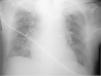

Un varón de 88 años con antecedentes de hipertensión arterial, diabetes y fibrilación auricular crónica, consultó por afasia. A su ingreso presentó convulsiones tónico clónicas generalizadas seguidas de un marcado deterioro en el estado de conciencia, por lo que se efectuó la colocación de un tubo orotraqueal y se comenzó con asistencia respiratoria mecánica. A las 36 horas el paciente fue extubado sin complicaciones. Al día siguiente la radiografía de tórax de control evidenció la presencia de una prótesis dental en el bronquio fuente izquierdo (fig. 1) que fue removida sin complicaciones mediante una fibrobroncoscopia. La aspiración de un cuerpo extraño habitualmente produce una obstrucción por encima de la glotis. En este caso la alteración en la deglución y la ausencia del reflejo tusígeno fueron determinantes para que la prótesis dental se impactase a nivel bronquial.